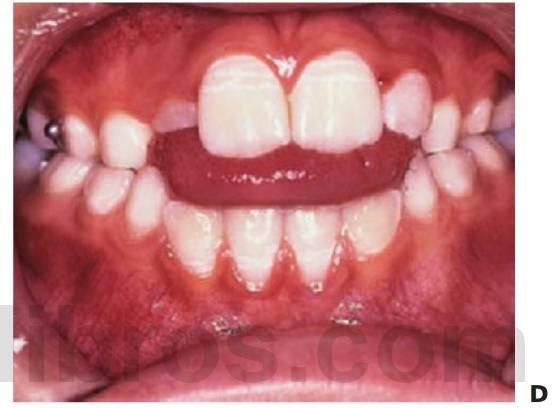

Como sucede con todos los aparatos removibles, el éxito del tratamiento depende de la cooperación y el cumplimiento por parte del paciente. Si estas cualidades se mejoran y el paciente se responsabiliza de llevar puesto el aparato, el tratamiento progresará de forma satisfactoria. De vez en cuando, la mordida cruzada también puede deberse a un incisivo inferior situado en sentido labial. Esto también debe corregirse pero depende del espacio disponible, y si no lo hubiera, el tratamiento definitivo debería retrasarse (fig. 11.11).